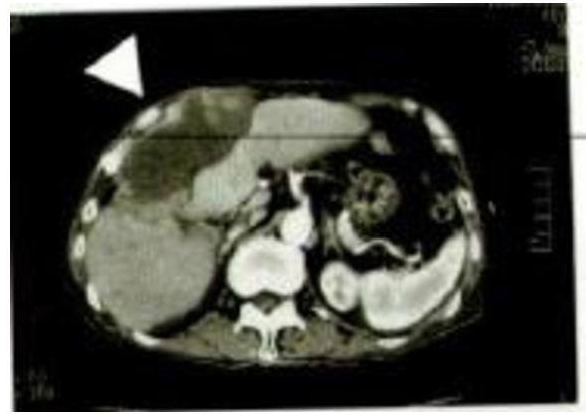

Imaginea CT stânga a fost luată în a 11-a lună de la

inițierea ingerării Agaricus.

Contrar declarației medicului curant, care susținea că mai are 3 luni de viață, imaginea de față indică o reducere majoră a zonei afectate de cancer.

Mărimea acesteia este de 33 mm x 24 mm. La măsurarea volumului s-a constatat o reducere de 30 de ori. În plus, au existat o serie de cazuri în care s-a considerat că Oyama Agaricus și-a manifestat eficacitatea și în mod separat. În multe cazuri, s-a apreciat că a sporit efectul terapeutic în tratamentul concomitent cu radioterapie și chimioterapie.